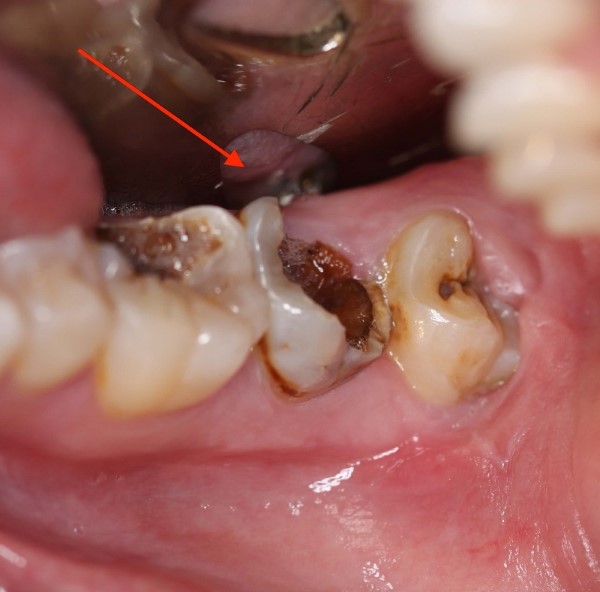

Nhức răng kinh khủng là tình trạng răng bị đau dữ dội, kéo dài và gây ra cảm giác khó chịu, ảnh hưởng nghiêm trọng đến chất lượng cuộc sống. Cơn đau có thể xuất hiện đột ngột hoặc từ từ tăng dần, kèm theo các triệu chứng như ê buốt, nhói, sưng nướu, khó nhai, khó mở miệng. Mức độ đau có thể khác nhau tùy thuộc vào nguyên nhân gây ra và tình trạng răng miệng của mỗi người.

Có nhiều nguyên nhân dẫn đến nhức răng kinh khủng, một số nguyên nhân phổ biến nhất bao gồm:

Cơn đau nhói đột ngột, bất thường thường xuất phát từ các vấn đề về tủy răng, như viêm tủy răng hoặc áp xe răng. Viêm tủy thường xảy ra khi vi khuẩn xâm nhập vào sâu trong tủy răng, gây ra viêm nhiễm và sưng tấy. Lúc này, các dây thần kinh bị kích thích dẫn đến cảm giác đau nhói dữ dội, lan tỏa đến cả vùng hàm và tai.

Một số trường hợp, nhức răng kinh khủng xuất hiện từng đợt, theo chu kỳ nhất định. Đây có thể là dấu hiệu của viêm nha chu hoặc các bệnh lý răng miệng khác. Viêm nha chu là tình trạng nhiễm trùng mô quanh răng, gây ra sưng nướu, chảy máu chân răng, thậm chí làm lỏng lẻo và mất răng.

Răng khôn khi mọc lệch hoặc mọc ngầm có thể gây ra nhiều vấn đề cho răng miệng, bao gồm nhức răng kinh khủng. Răng khôn bị mắc kẹt trong xương hàm, gây áp lực lên các răng kế cận, tạo ra cảm giác đau nhói, sưng nướu, khó chịu. Ngoài ra, răng khôn mọc lệch còn tạo điều kiện cho vi khuẩn phát triển, gây viêm nhiễm, dẫn đến tình trạng nhức răng nặng hơn.